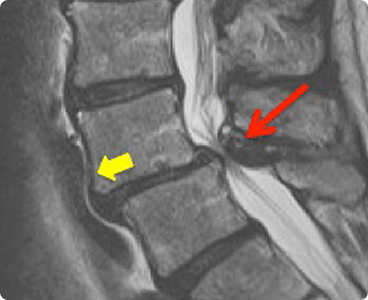

Spinal stenosis is the narrowing of spaces in the spine (backbone), which causes pressure on the spinal cord and nerves.

In lumbar stenosis, the spinal nerve roots in the lower back become compressed and this can produce symptoms of sciatica—tingling, weakness or numbness that radiates from the low back and into the buttocks and legs—especially with activity. For lumbar stenosis, flexing forward or sitting will open up the spinal canal by stretching the ligamentum flavum and will relieve the leg pain and other symptoms, but the symptoms will recur if the patient gets back into an upright posture. Numbness and tingling can accompany the pain, but true weakness is a rare symptom of spinal stenosis.

MRI scan and/or a CT with myelogram can show the tight canal and spinal cord pinching associated with myelopathy from stenosis of the cervical spine.